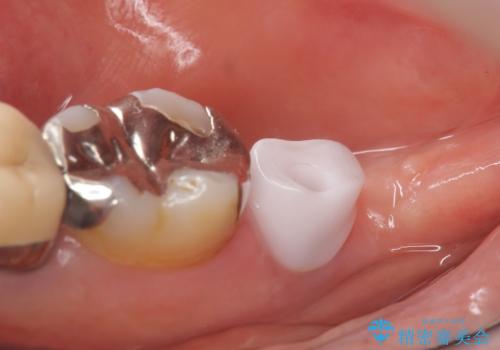

インプラントと骨の定着を待った後に二次手術を行い、カスタムアバットメント、オールセラミッククラウンによる補綴を行いました。

カスタムアバットメントは患者様それぞれの歯茎に合わせて製作されたオーダーメイドのアバットメントです。

既製のアバットメントに比べ適合がよく、高い清掃性を誇ります。

今回用いたオールセラミッククラウンはジルコニアフレームという白い素材の上にセラミックを盛っているため、審美性が非常に高いのが特徴です。

また、ジルコニアは人工ダイヤモンドの材料にも使われているほど高い強度を持っており、そのためオールセラミッククラウンは審美性だけでなく、奥歯やブリッジの補綴も可能とするクラウンです。